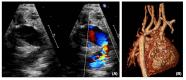

Hypoplastic left heart syndrome (HLHS) is a spectrum of left heart underdevelopment leaving the left side unable to support the systemic circulation. If active management is pursued, then the condition is managed with staged palliation to the Fontan circulation, leaving a systemic right ventricle. Through all surgical stages, and even after completion of Fontan, there are multiple areas that may require intervention, most frequently the branch pulmonary arteries which are essential to a successful Fontan circulation. Echocardiography is the mainstay of assessment, but there is an increasing use of magnetic resonance imaging (MRI) and computed tomography (CT) particularly in relation to extracardiac structures which can be more challenging with echocardiography. Both MRI and CT require set-up, experience and training, and usually sedation or anesthetic in smaller children, but can provide excellent imaging to guide interventions. Cardiac MRI is also able to quantify right ventricular (RV) function which can be challenging on echocardiography. This article describes the modalities available and their use in assessing patients with HLHS prior to catheter interventions.